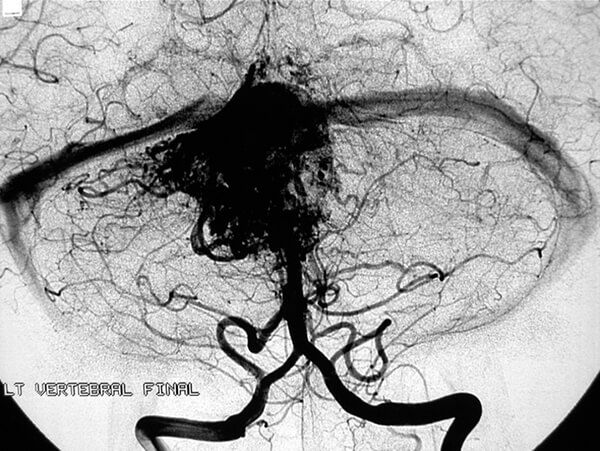

- Μπορεί να είναι πολλαπλά, ακόμη και εκτός της πλήρους έκφράσεως του συνδρόμου von Hippel Lindau. Εντοπίζονται στον οπίσθιο κρανιακό βόθρο ή τον νωτιαίο μυελό. Αν και είναι σαφώς αφοριζόμενοι όγκοι, στερούνται κάψας. Συχνά αντλούν αιμάτωση από την επαφή τους με το παρακείμενο εγκεφαλικό παρέγχυμα. Σε μερική αφαίρεση, υποτροπιάζουν συχνά. Δεν προκαλούν απομακρυσμένες μεταστάσεις.

- Τυπικά παρουσιάζονται λόγω χωροκατακτητικών σημείων με αύξηση της ενδοκρανίου πιέσεως και υδροκεφαλία από απόφραξη της 4ης κοιλίας. Σε μυελική εντόπιση, το εντοπισμένο άλγος με προϊούσα κινητικο-αισθητική διαταραχή, οδηγεί χωρίς θεραπεία σε παραπληγία ή τετραπληγία. Η αιμορραγία είναι σπάνια.